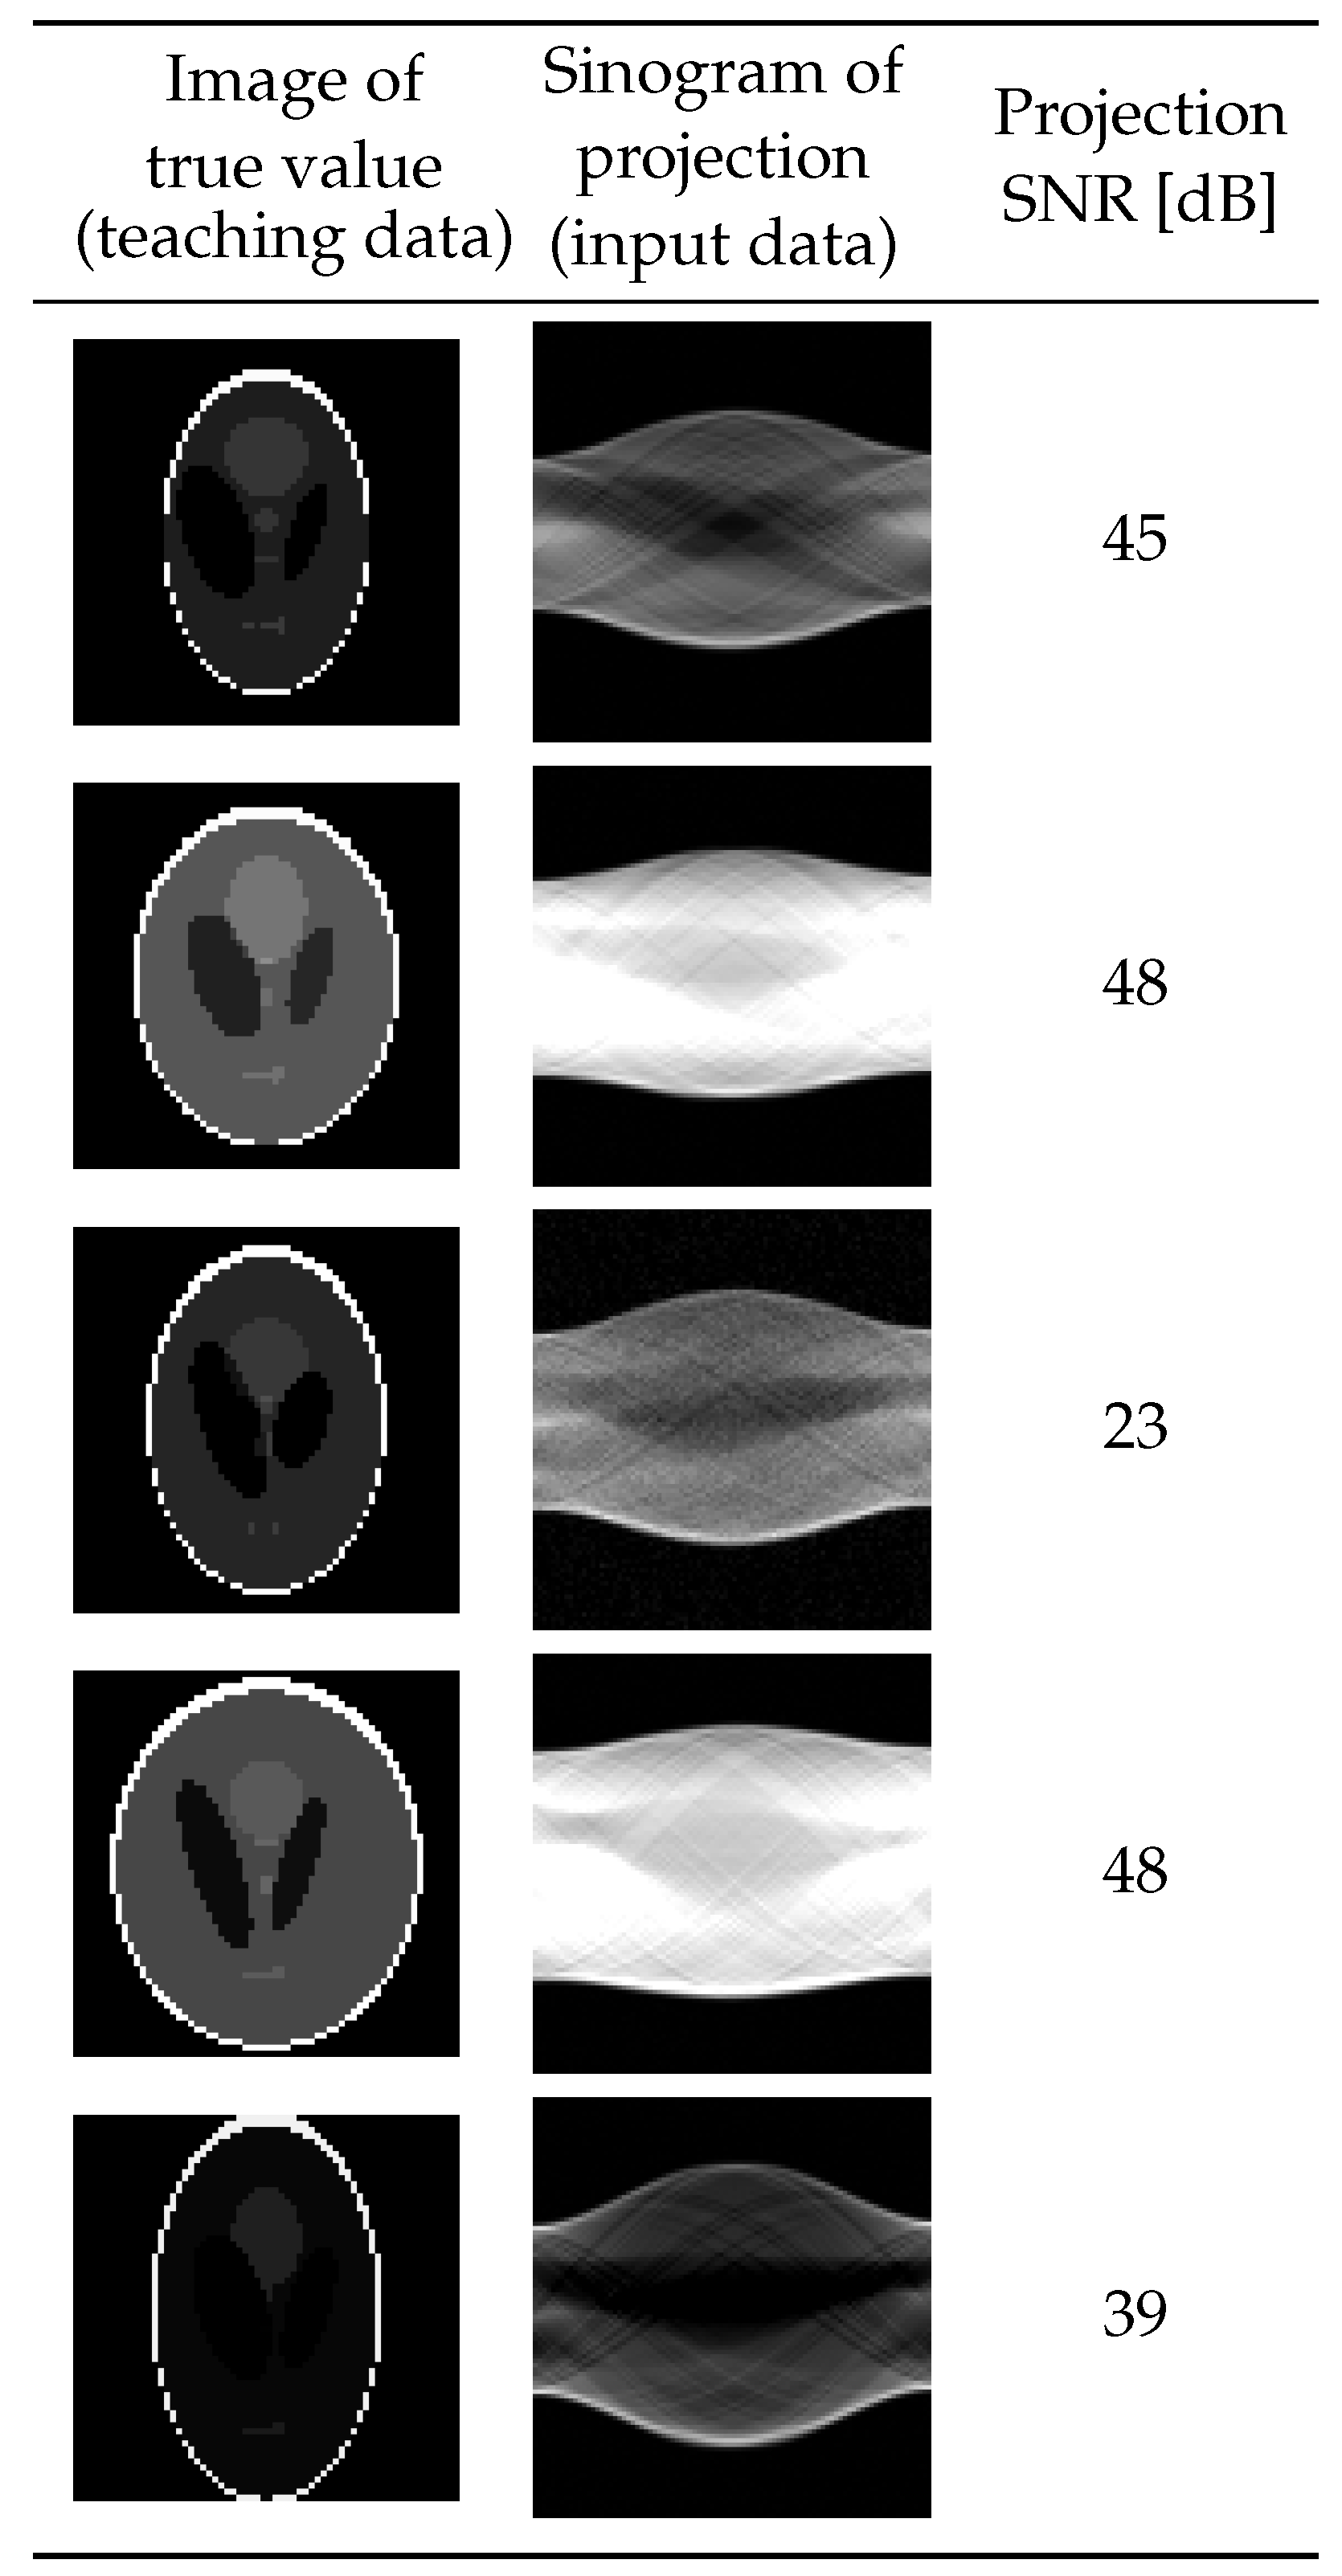

In this section, we present the results of an experiment on the proposed system using 5000 pairs of input and teaching data generated by numerical simulations. We generated teaching data in the form of -pixel images deformed by changing the attributes of each oval, i.e., its intensity, size, position, and rotation angle, from the Shepp–Logan phantom [54] shown in Figure 4a. The attributes were varied in the ratio ranges shown in Table 1 from that of the base phantom by using uniform random numbers. The MATLAB (MathWorks, Natick, MA, USA) function phantom [55] generated the images. To avoid generating extremely large or small ovals that should not be considered, some common deformation rates were chosen for one attribute in some of the sets of ovals in one phantom. The input data were projections calculated by Equation (1) by using a common projection operator A, projection noise , and the target image x as the corresponding teaching data. The projection operator A, represented as a matrix, was simulated on the basis of the Radon transform assuming parallel projections from 90 directions with 95 detectors, so and . The signal-to-noise ratio (SNR) for each projection was selected so as to be uniformly distributed in the range of 20 dB to 50 dB. Figure 5 shows the resulting experimental histogram of SNRs, while Figure 6 shows samples of learning data generated by the above procedure.

Figure 6.

Samples of learning data.

To evaluate the performance of the learned optimizer , we validated it on a test dataset consisting of data not included in the training and validation datasets. The properties described below are common to all of the test datasets. We will discuss the results for five of the test data pairs shown in Figure 9. The first test data item () was a pair of a projection with an SNR of 20 dB and the expected reconstructed image . In the second and third test data pairs ( and 3), the expected reconstructed images and equaled but with different Sn Rs of the projection. On the other hand, in the fourth and fifth test data pairs ( and 5), the expected reconstructed images and were different from and from each other, but the noise levels of the projections were 20 dB.

Figure 9.

Dataset for testing.